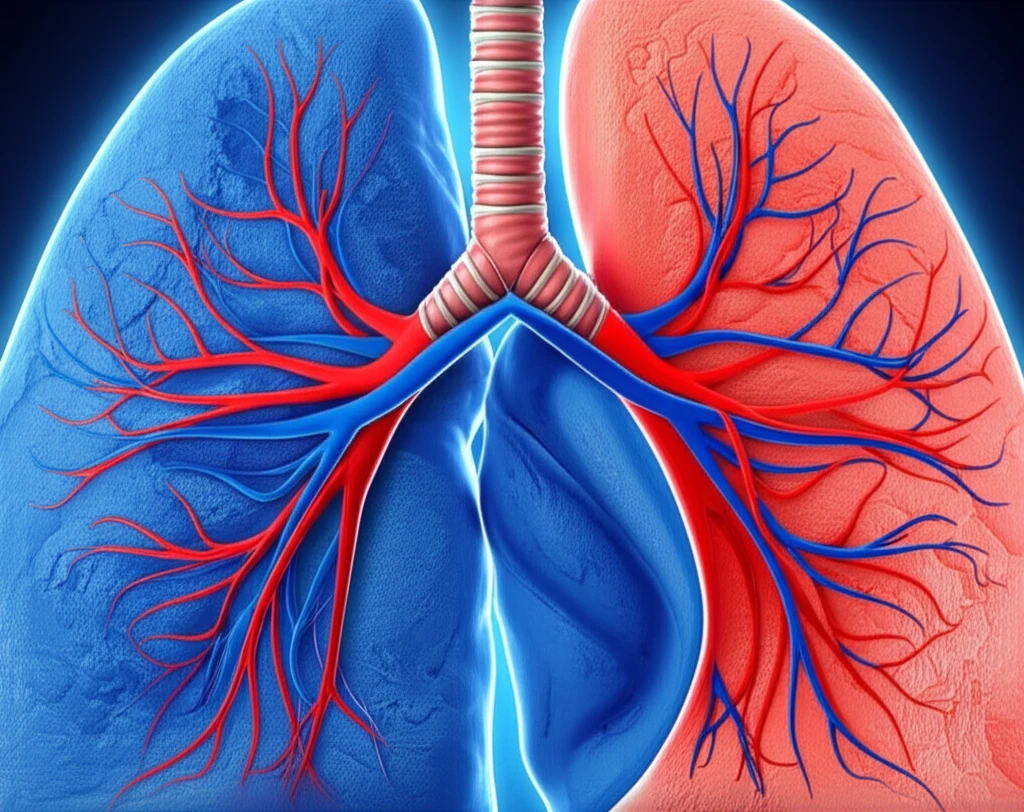

Lung cancer remains a formidable challenge, but new research is shedding light on how we can better understand and combat this disease. A recent study has uncovered a fascinating link between blood flow patterns within tumors and the specific type of lung cancer a patient has. This discovery is a crucial step towards more personalized and effective treatment strategies.

Lung cancer isn't just one disease; it's an umbrella term for various types, the most common being adenocarcinoma (AC) and squamous cell carcinoma (SCC). Each type has its own unique characteristics, including how it interacts with the body's blood supply. Understanding these differences is essential because it can dramatically impact how well a patient responds to treatment.

This study investigated the blood flow (BF) in these two lung cancer subtypes using a sophisticated imaging technique called CT perfusion. The researchers aimed to determine whether the BF patterns differed between AC and SCC, and if so, what those differences could mean for treatment planning and patient outcomes. This exploration could lead to more tailored therapies, potentially saving lives.

The study's core focus was on the blood flow characteristics of AC and SCC tumors. By using CT perfusion, researchers could visualize and quantify the blood supply within the tumors. The results were striking: AC tumors showed significantly higher blood flow than SCC tumors. This finding isn't just a technical detail; it has profound implications.